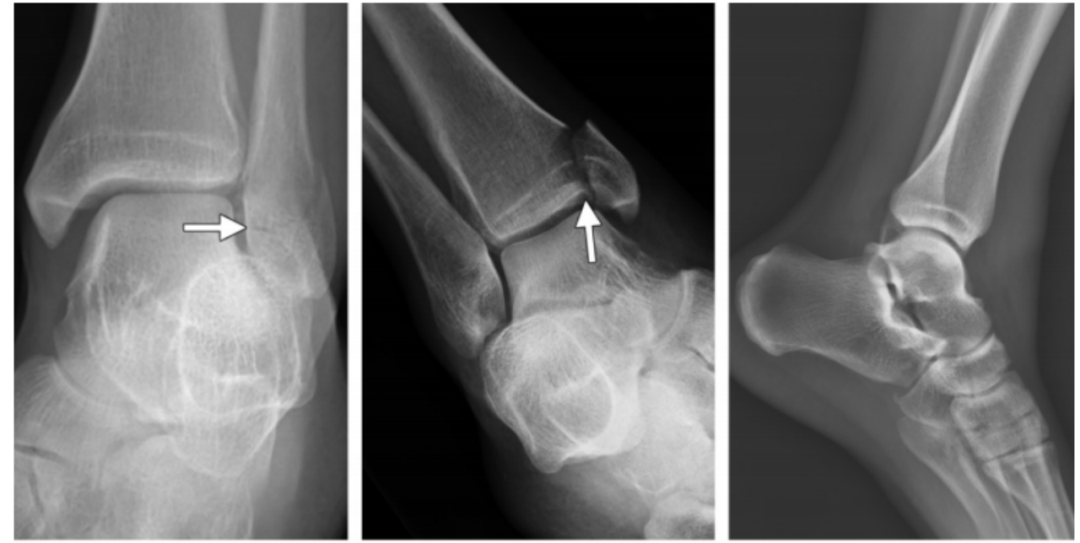

2、旋后(内翻)外旋损伤(简称 SE)

损伤时患足呈旋后位,距骨外旋,胫骨内旋,因此在损伤初期三角韧带松弛,当距骨继续外旋,腓骨受到向外后推挤,胫腓下联合前韧带及三角韧带紧张。

分为四度:

I 度:首先在外旋力作用下发生下胫腓前韧带断裂,该韧带断裂可以发生在腓骨附着点撕脱骨折(Wagstaffe 骨折)、韧带本身或者胫骨附着点撕脱骨折(Tillaux-Chaput 骨折)。

I 度损伤 X 线显示:胫腓骨间隙轻微增宽,提示下胫腓前韧带断裂;软组织肿胀;侧位片显示后踝未发生骨折。此型在 X 线上是隐匿的。

Ⅱ 度:由于距骨给腓骨施加了旋转力,导致腓骨在胫骨关节面顶部发生斜行或螺旋形骨折,骨折线一般自前下方斜向后上方。

II 度损伤 X 线片显示:胫腓骨间隙变宽,提示下胫腓前韧带断裂;腓骨螺旋形骨折;侧位片显示腓骨骨折位于下胫腓联合水平,骨折线由前下到后上,后踝无骨折。

Ⅲ 度:若外旋的力量进一步作用,可导致下胫腓后韧带断裂,或韧带在腓骨后结节附着点撕脱,或其胫骨附着点撕脱骨折(Volkmann 骨折)。

IV 度损伤 X 线片显示:胫骨腓骨间隙变宽,提示下胫腓韧带联合断裂;腓骨螺旋形骨折,腓骨骨折位于下胫腓联合水平,骨折线由前下到后上,内踝间隙增宽,提示三角韧带断裂;侧位片显示后踝无明显骨折,但下胫腓后韧带可能断裂。